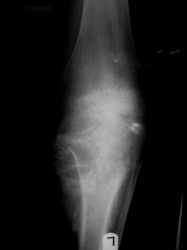

Anatomic sites of developing an osteosarcoma:

- Long Bones (Most common: 70%-80% of cases)

- Most (90%) arise from the metaphysis of the bone; 10% from the diaphysis

- Thus in most instances, the tumor arises next to a joint

- Distal Femur: most common site (40%; about twice as common as proximal tibia)

- Proximal Tibia: Second most common site

Radiographic Presentation: Conventional Osteosarcoma

There are 3 radiographic presentations for osteosarcomas, depending upon the amount of osteoid/ossification and calcium deposition:

- Mixed sclerotic and lytic, permeative lesion most common radiographic presentation

Conventional osteosarcomas are permeative lesions on plain radiographs (borders of the lesion cannot be clearly delineated)

- Wide zone of transition from lytic/sclerotic areas of tumor to normal bone

- Makes borders of lesion hard to define

- Most (90%) arise from the metaphysis of the bone

- Rarely (10%) arise from the diaphysis

- Most conventional osteosarcomas (90-95%) extend through the bone into the soft tissues and form a soft tissue mass outside of the bone